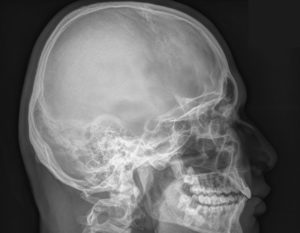

Как правило, рентген проводится в двух проекциях:

- прямой (фронтальной);

- боковой (сагиттальной).

Это объясняется тем, что рентгенограмма — это плоское изображение трехмерного объекта. Чаще всего достаточно двух проекций, чтобы установить локализацию патологических изменений.

На первом этапе пациента располагают таким образом, чтобы боковая поверхность его черепной коробки находилась параллельно функциональной поверхности, и делают снимок в сагиттальной проекции.

Центральный рентгеновский луч должен быть направлен на пару сантиметров выше прямой, соединяющей верхненаружный глазничный край с наружным слуховым проходом.

Если все сделано правильно, то на снимке клиновидные отростки, верхние стенки глазницы и наружные слуховые проходы будут накладываться друг на друга.

Качественно сделанный снимок в сагиттальной проекции позволяет специалисту изучить состояние как черепной коробки в целом, так и отдельных ее сегментов, в частности:

- черепных швов;

- турецкого седла;

- лицевого скелета;

- свода и основания.